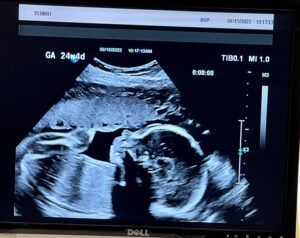

Reversing Tubal Rings, Baby Boy 24 Weeks Strong And Healthy!

24 Weeks!

Our baby boy growing strong and healthy!

Patient age: 35

Tubal ligation type: Tubal rings (bands)

Patient hometown: Johnstown, Pennsylvania